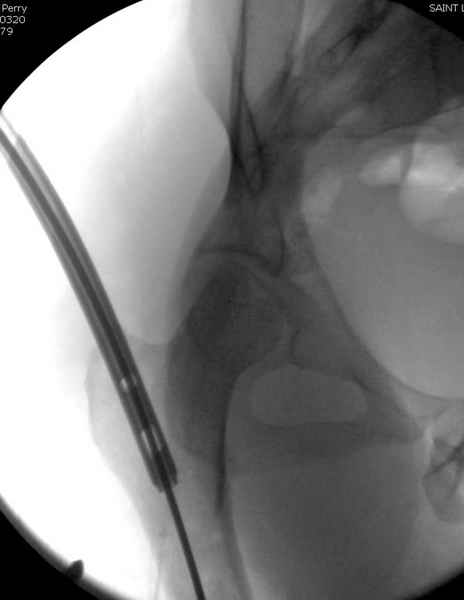

Второй случай тоже репозиция из малого доступа, больному 19 лет, множественные огнестрельные повреждениия конечностей, живота и черепа, правая конечность холодная, без пульсации. Ортопедический диагноз: огнестрельный перелом правого бедра. При срочной ангиографии повреждения сосудов не подтвердилось, конечность из-за ургентности состояния больного зафиксирована временным наружным фиксатором и больной оставлен на операционном столе для срочной лапаротомии хирургической службой.